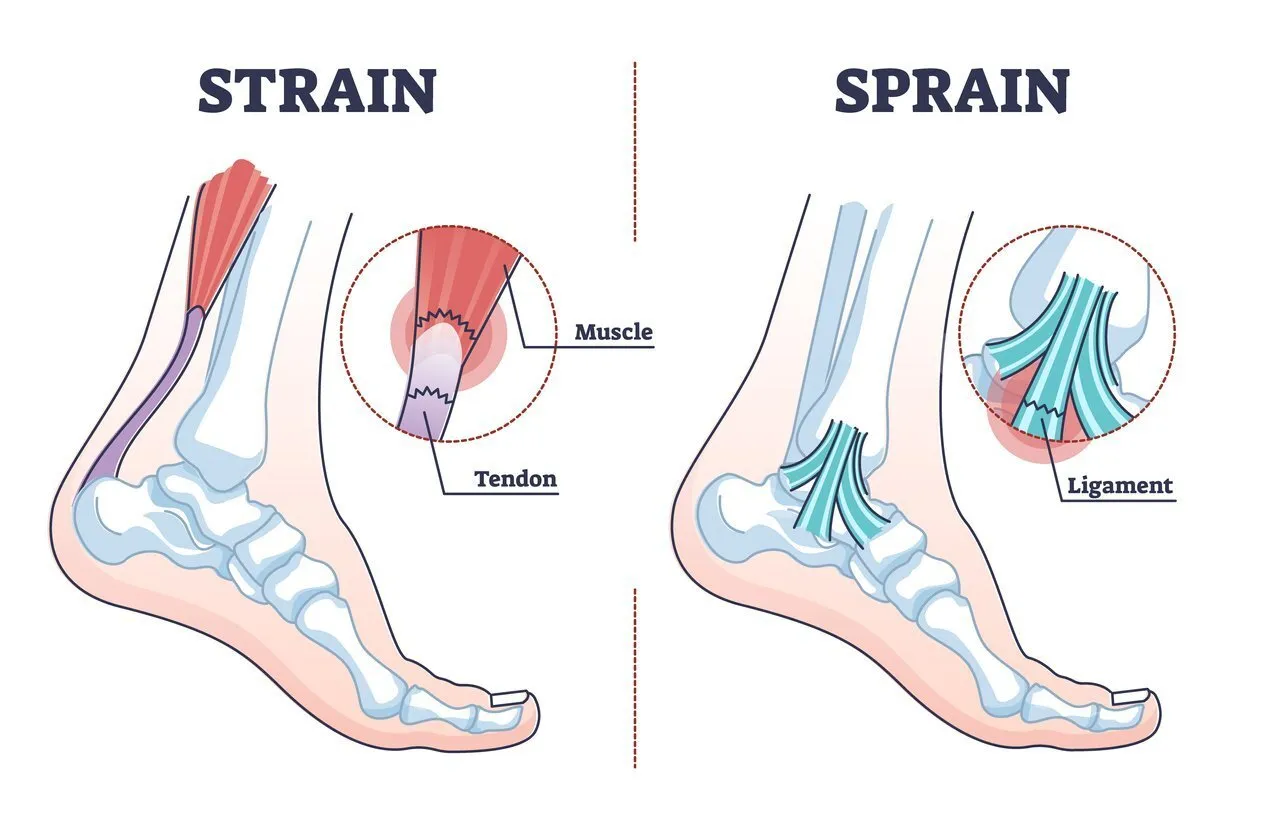

رباط ها و تاندون ها هر دو از بافت همبند فیبری تشکیل شده اند، اما شباهت در اینجا به پایان می رسد. رباط ها به صورت نوارهای متقاطع ظاهر می شوند که استخوان را به استخوان می چسبانند و به تثبیت مفاصل کمک می کنند. به عنوان مثال، رباط صلیبی قدامی (ACL) استخوان ران را به استخوان ساق پا متصل می کند و مفصل زانو را تثبیت می کند.

تاندون ها که در هر انتهای عضله قرار دارند، عضله را به استخوان متصل می کنند. تاندون ها در سرتاسر بدن، از سر و گردن تا پاها یافت می شوند. تاندون آشیل بزرگترین تاندون بدن است. ماهیچه ساق پا را به استخوان پاشنه می چسباند. تاندون های روتاتور کاف به چرخش شانه به جلو و عقب کمک می کنند.

هنگامی که یک رباط بیش از حد کشیده یا پاره می شود، منجر به چیزی می شود که از نظر فنی به آن رگ به رگ شدن می گویند. بسیاری از رگ به رگ شدن ها به طور ناگهانی یا در اثر زمین خوردن، حرکت نامناسب یا ضربه اتفاق می افتد.

پیچ خوردگی معمولا در مچ پا، زانو یا مچ دست اتفاق می افتد. به عنوان مثال، یک گام اشتباه می تواند باعث شود که مچ پای خود را در موقعیتی نامناسب بپیچانید، رباطی را بشکافید و باعث بی ثباتی یا لرزش مچ پا شود. ممکن است هنگام آسیب دیدگی صدای پارگی بشنوید یا احساس پارگی کنید. زمانی که دست دراز کرده خود را برای شکستن زمین دراز میکنید، مچ دست اغلب رگ به رگ میشود، فقط برای اینکه مچ دست به عقب باز شود. این افزایش کشش رباط را بیش از حد کشیده می کند.

تاندون

زمانی که تاندون بیش از حد کشیده یا پاره می شود، به آن فشار می گویند. نواحی متداول تحت تاثیر فشارها ساق پا، پا و پشت هستند. کشیدگی ها اغلب نتیجه حرکات معمولی و دو و میدانی هستند. ورزشکارانی که بدون زمان کافی برای استراحت و ترمیم عضلات در بین جلسات تمرین بیش از حد بدن خود را تمرین می دهند، در معرض خطر بیشتری هستند.

بسیار شبیه به رگ به رگ شدن، علائم شامل درد و تورم است. همچنین ممکن است گرفتگی و ضعف عضلانی را تجربه کنید.